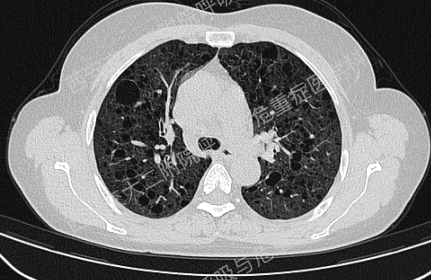

上图与Case 2比较相似,所以诊断LAM没有问题,还需进一步排查系散发型还是结节性硬化症累及。

影像学评估发现患者多系统受累(肝脏错构瘤、双肾血管平滑肌脂肪瘤、颅脑多发异常信号结节)。追问病史,患者本人无皮疹、癫痫及智力低下;患者儿子有面部皮脂腺瘤,无癫痫及智力低下,胸腹部CT未见异常,皮肤科已确诊结节性硬化症;患者女儿面容及智力均正常;建议患者进一步行TSC基因检测,结果回报TSC2突变,结节性硬化症诊断明确。

患者尝试口服西罗莫司2mg/日,消化道难以耐受,减至1mg/日,仍有恶心等不适,自行停药,不愿再尝试药物治疗,目前随访观察中。